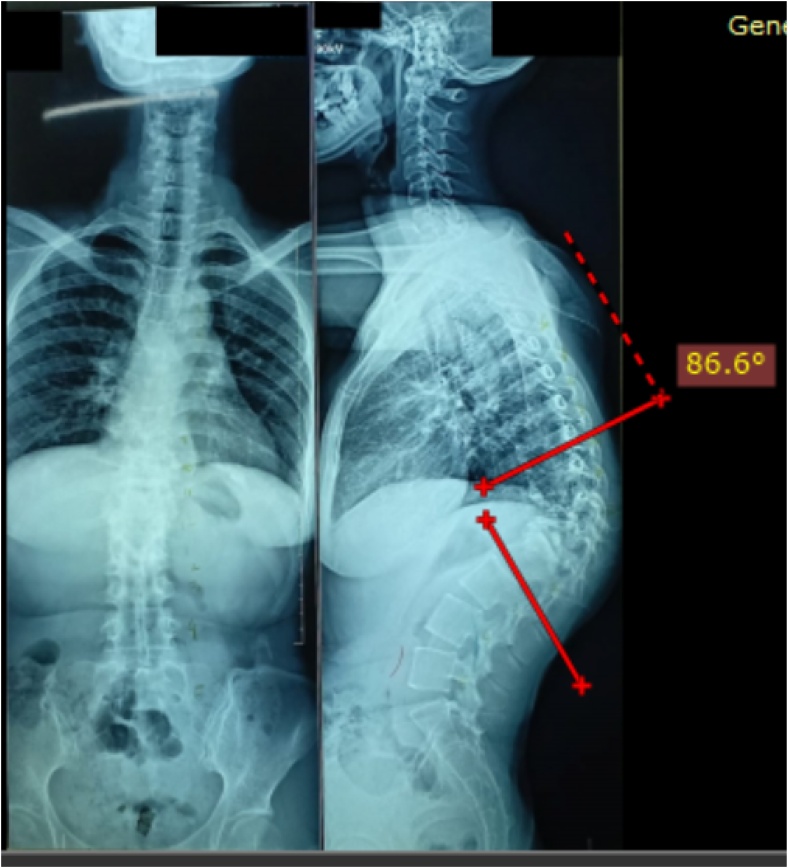

A 27 years old female patient presented with kyphotic deformity of 86.6 degree at the thoracolumbar area from thoracal (Th)10 – Lumbar (L) 2, with destruction of Th11, 12, and L1 due to spine tuberculosis as demonstrated in Fig. 1. Preoperative evaluation showed her neurologic status was without abnormality. She underwent laminectomies, PVCR, one level Smith Peterson Osteotomy (SPO), posterior instrumentation by pedicle screws from Th 8,9,10 and L2,3,4, and fusion by local bone graft.

Fig. 1.

Patient with Thoracal Kyphosis of 86.6 degree. The measurement was carried out before the index surgical procedure.